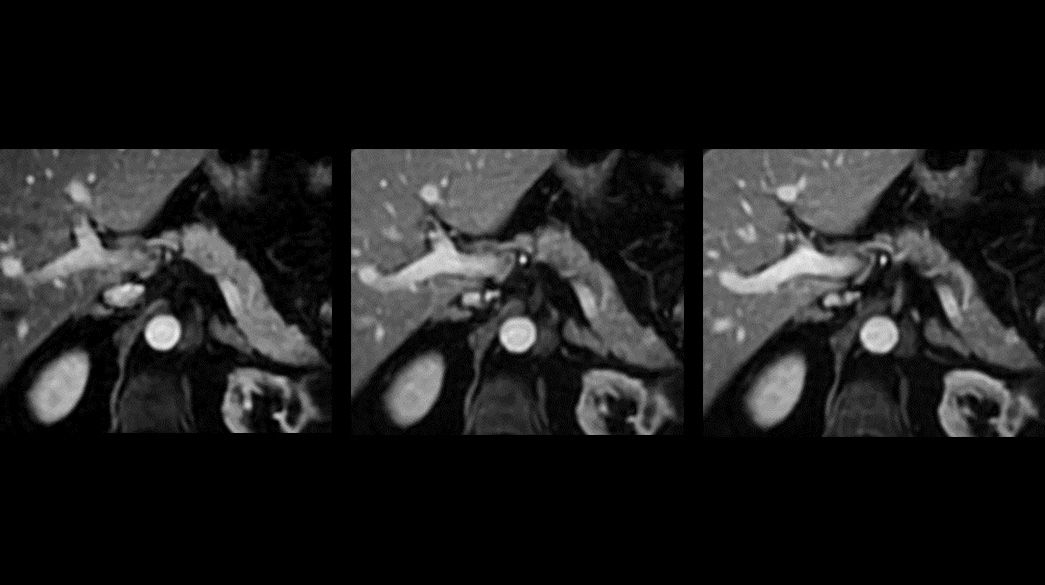

Body MRI for SIGNA™

Fast body MR imaging techniques to capture breast, abdominal and pelvic anatomy on any patient, with great flexibility.

Clinical Body MRI

Body MRI imaging applications